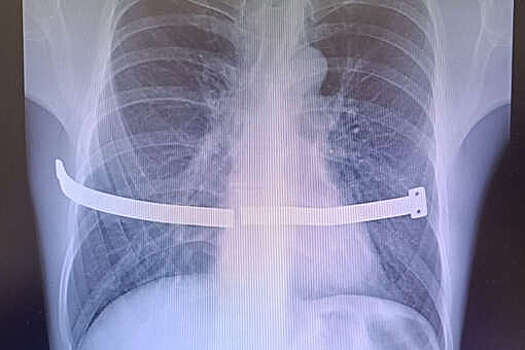

Врачи Сургутского травматологического центра спасли мужчину, беспечность которого едва не привела к серьезным повреждениям внутренних органов. Случаем из практики поделились в пресс-службе медицинского учреждения. Пациент 17 лет проходил с металлической пластиной в груди, которая, ожидаемо, раскололась, так как не была предназначена для столь долгой "эксплуатации". Конструкцию установили мужчине для коррекции воронкообразной деформации груди. Устройство следовало удалить спустя четыре года, но пациент не торопился с операцией. В итоге пластина разломилась пополам и один из ее краев стал упираться в оболочку сердца. Из-за сильных болей пациент обратился к медикам, и операции избежать не удалось. "Пациент все-таки расстался с пластиной. Хирурги успешно извлекли ее, несмотря на технические сложности. За многие годы металл уже сросся с костной тканью, пришлось частично резецировать ребро", - рассказали в пресс-службе, отметив, что это не повлияет на качество жизни. Медики отметили, что подобные вмешательства малотравматичны и мужчина зря подвергал себя рискам, отсрочивая ее.